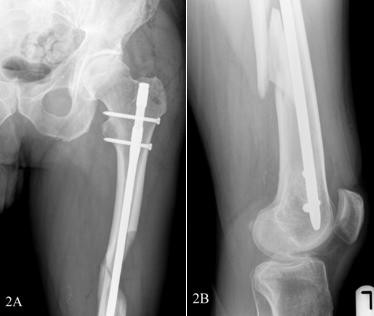

Un clou intramédullaire fémoral est un dispositif médical conçu pour stabiliser et favoriser la cicatrisation des fractures du fémur.Il se compose d'une tige métallique qui est insérée dans le centre creux du fémur, offrant stabilité et soutien pendant le processus de guérison.Le clou est généralement en titane ou en acier inoxydable et est disponible en différentes tailles pour s'adapter aux différentes anatomies des patients.

Après avoir créé un point d'entrée dans le fémur proximal, le chirurgien insère avec précaution le clou intramédullaire fémoral dans le canal médullaire.Un guidage fluoroscopique est utilisé pour assurer un placement et un alignement précis.Le clou est avancé à travers l'os, réalignant tous les fragments déplacés et rétablissant l'alignement anatomique approprié.

Une fois le clou correctement positionné, des vis de verrouillage sont insérées pour fixer le clou dans l'os.Ces vis offrent une stabilité supplémentaire et empêchent les mouvements de rotation ou axiaux des fragments de fracture.Le nombre et le placement des vis dépendent du type de fracture et de la préférence du chirurgien.